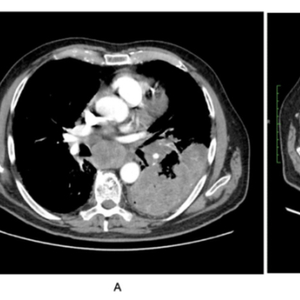

患者符合接受卡铂-依托泊苷方案的条件,早期治疗耐受性良好。经过两个周期的细胞毒性处理后,CT示存在部分好转(图2B),四个周期后持续好转(图2C)。治疗耐受性良好,达到了4个月PFS。